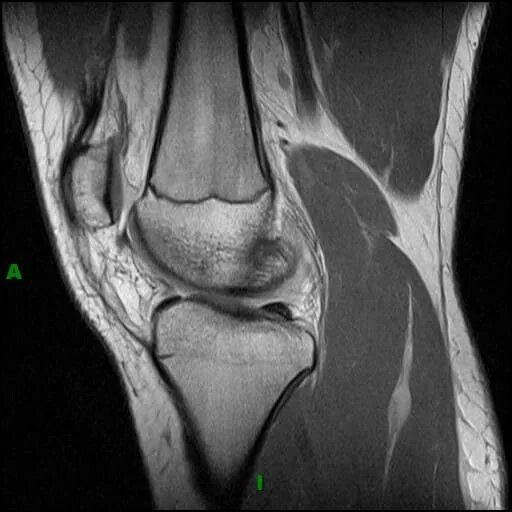

Что такое синовит коленного сустава на мрт